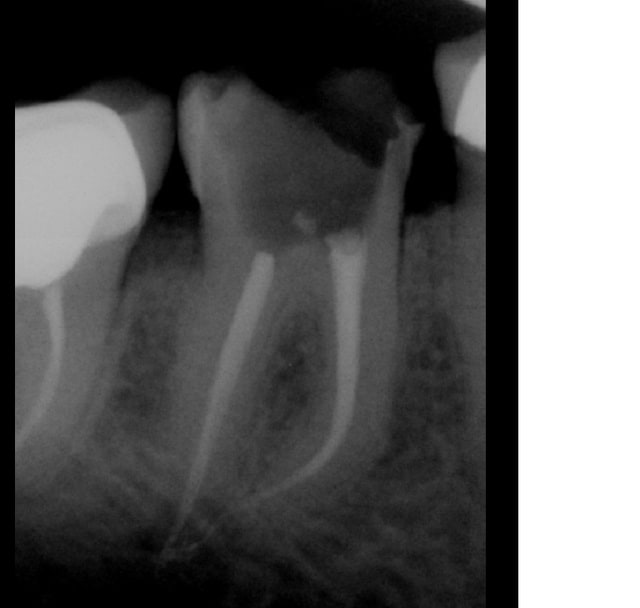

tout à fait d'accord avec toi, après j'aurai pas mis ces radios pour illustrer mes dires. Il me semble que les 2 apex aient été gentiment surinstrumentés à moisn que ce soit un défaut de la radio